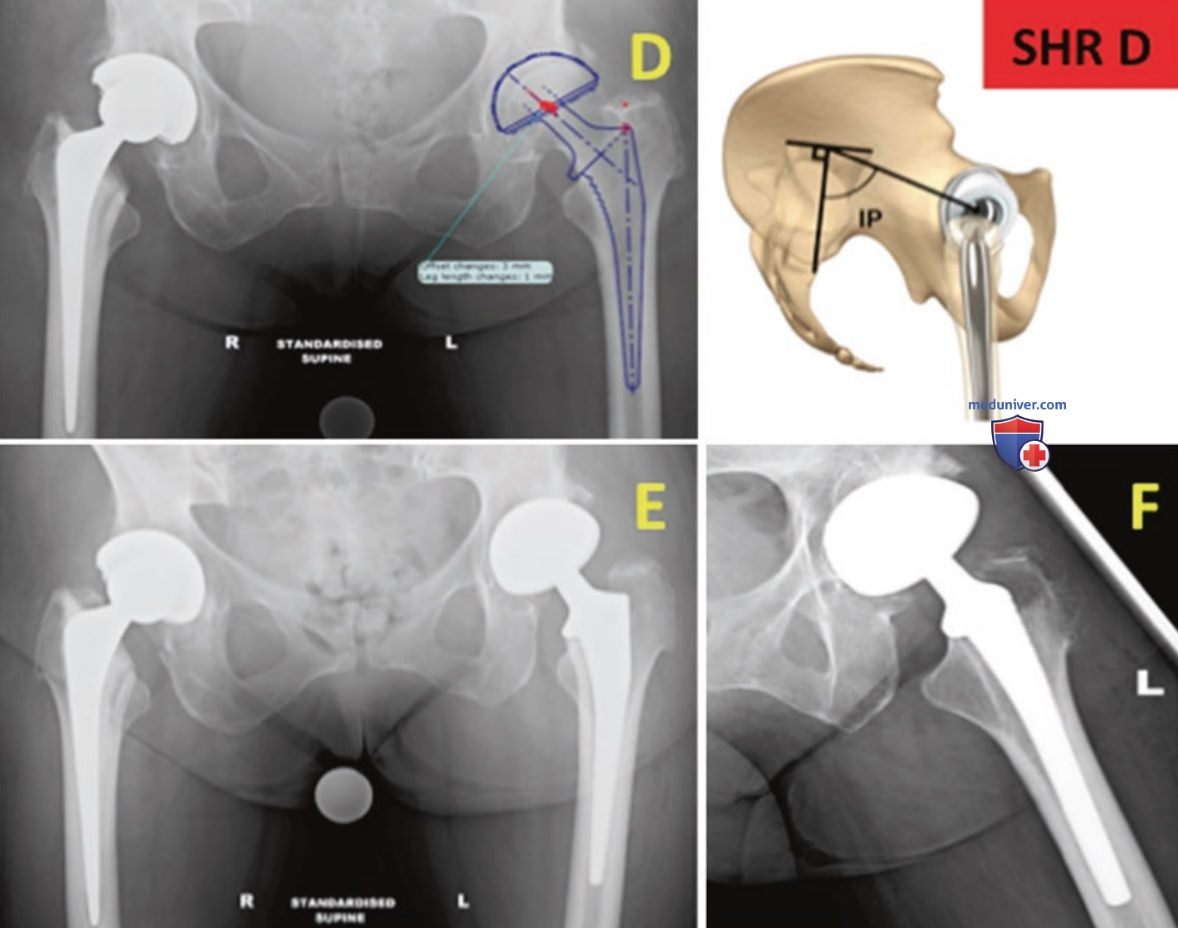

Замена обоих тазобедренных

Замена обоих тазобедренных 88 фото